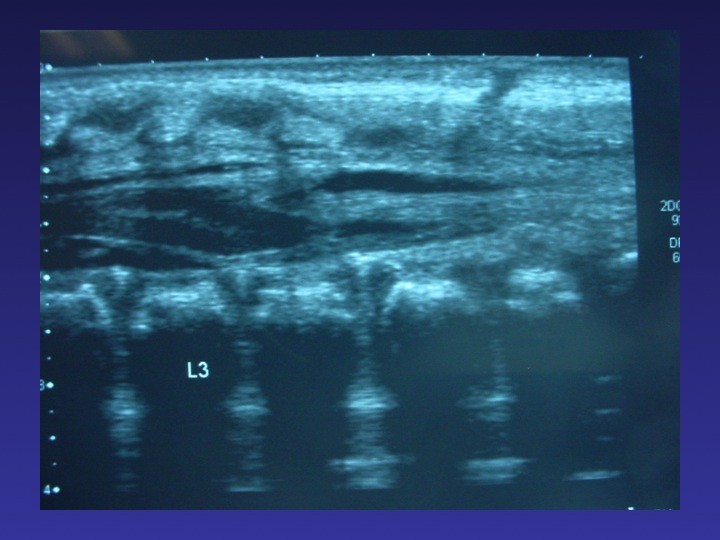

TABLE RONDE – La moelle attachée de l’enfant et de l’adolescent : diaporama 1

TABLE RONDE – La moelle attachée de l’enfant et de l’adolescent : diaporama 2